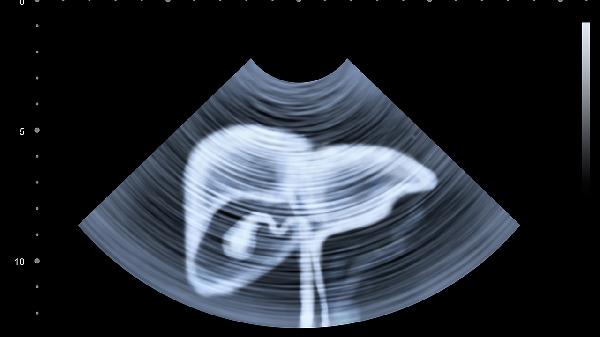

腹部彩超需要空腹8小时以上,以确保检查结果的准确性。空腹可以减少胃肠道内的气体和食物残渣,避免干扰超声波成像,尤其是针对肝胆胰脾等器官的检查。

腹部彩超检查前通常需要空腹8-12小时。这是因为进食后,胆囊会收缩并排出胆汁,导致胆囊壁增厚或胆囊内胆汁减少,影响医生对胆囊病变的判断。同时,食物在胃内的残留会干扰胰腺、肝脏等器官的显影效果。建议前一天晚餐后不再进食,检查当天早上保持空腹状态。